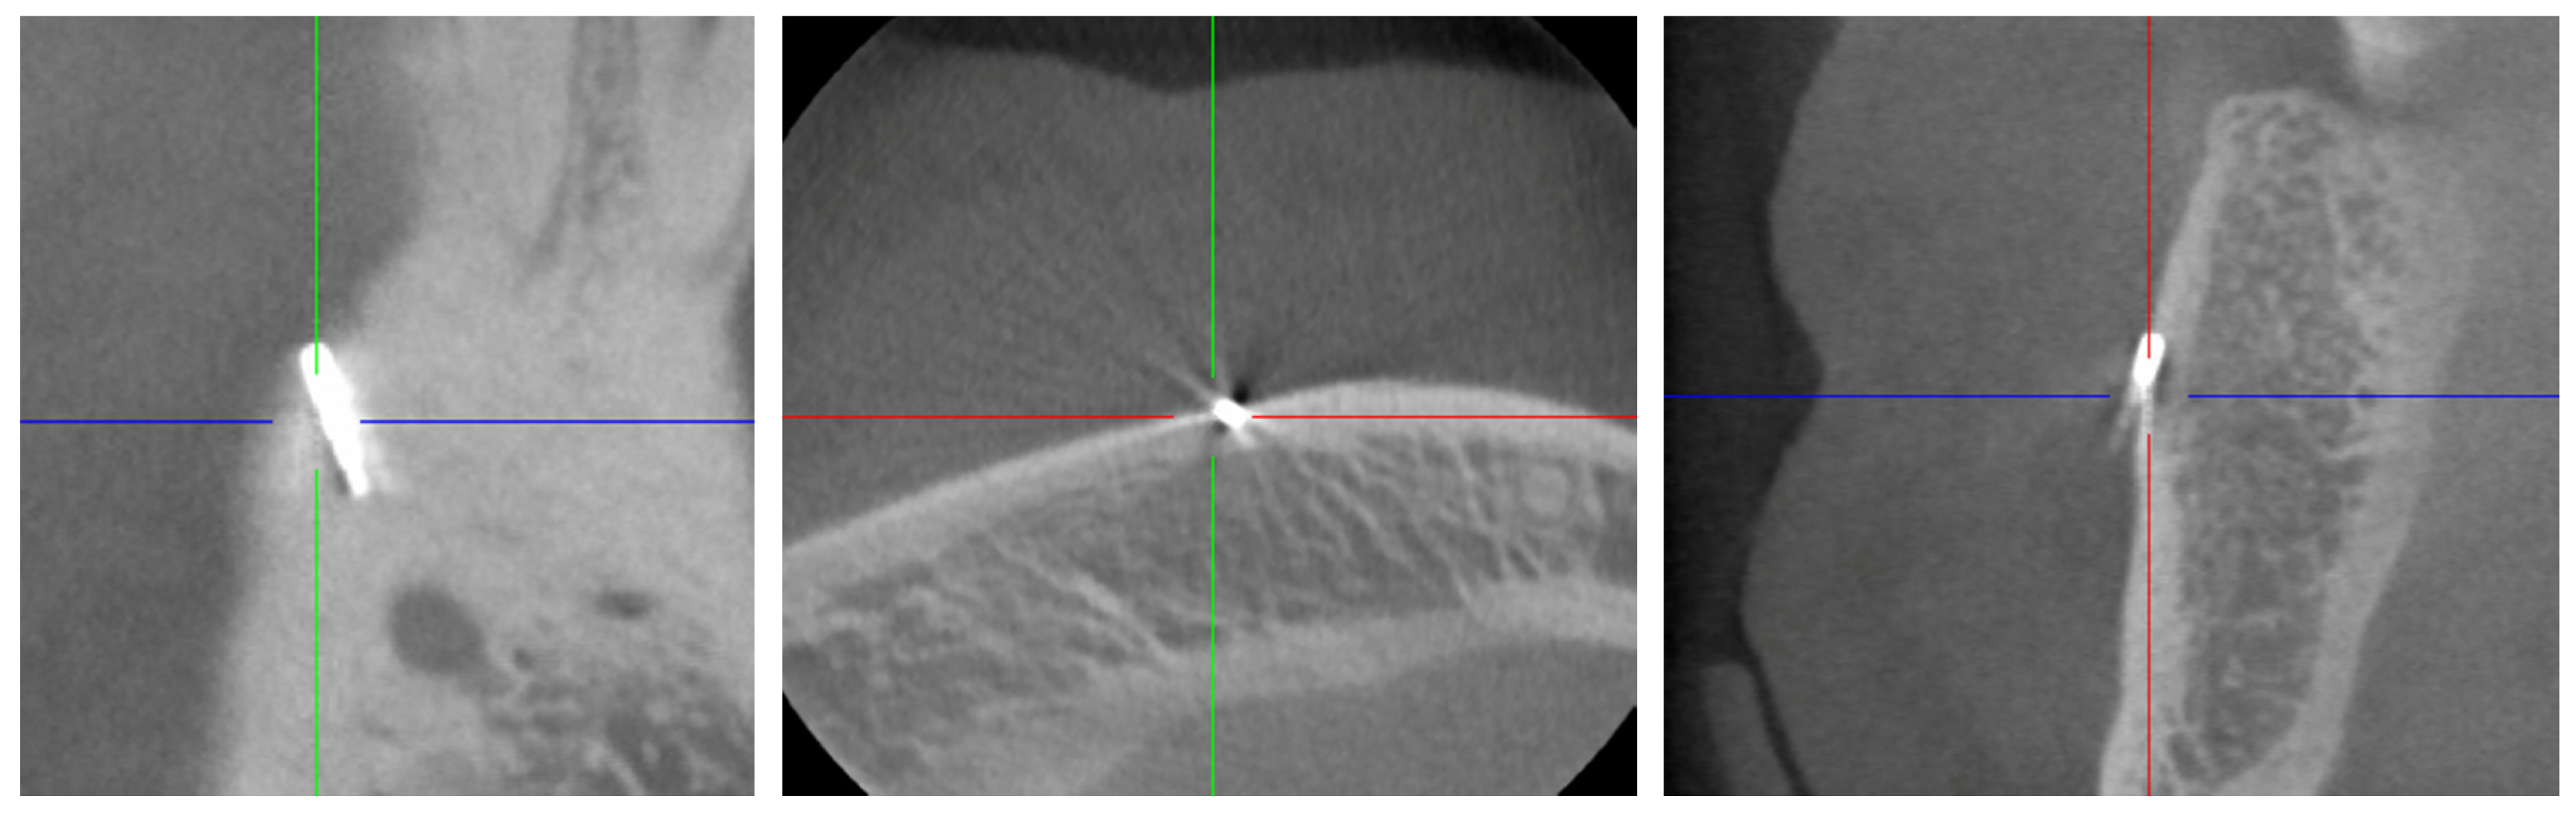

2.2. Digital Volume Tomography (DVT)

For the presurgical planning, a three-dimensional imaging using cone-beam tomography (CBCT) was made (Figure 2), using a MORITA 3D Accuitomo 170 (MORITA Europe, Jordi Röntgentechnik AG, Münchenstein, Switzerland) with a spatial resolution (voxel edge length) of 0.08 mm. The recording time was 17.5 s at 90 kV and 5 mA (pulsed).

Figure 2.

Cone-beam tomography showing the metallic opacity compatible with a broken tip of a periodontal probe. No close relationship to the mental nerve canal or supplying vessels was evident.

An opacity corresponding to the findings described in the OPT, but buccally perforating the cortical bone, was found. The shape, which was typical for a periodontal probe of the type AE P OWB (Michigan O with Williams Markings), led us to suspect that it was a broken periodontal probe tip made of medical steel. A possible differential diagnosis could be excluded with certainty, despite some artefacts.